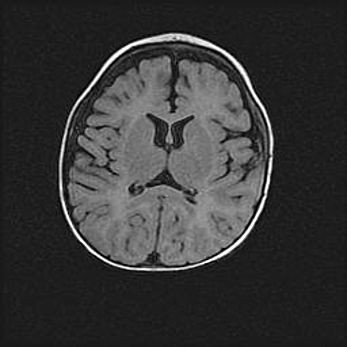

Наружная гидроцефалия с возможной атрофией височных областей.

Возраст: 28 дней

Вес: 3670 г

Пол: мужской

Окружность головы: 38 см

Срок гестации: 40 недель

Гидроцефалия головного мозга у новорожденных – это заболевание, которое характеризуется скоплением избыточного количества спинномозговой жидкости в желудочковой системе головного мозга в результате затруднения её перемещения от места выработки к месту поглощения в кровеносную систему или вследствие нарушения абсорбции. При открытой наружной форме гидроцефалии у новорожденных расширяются и переполняются субарахноидные пространства.

При нормотензивных  формах,  которые,  как  правило,  являются  следствием  перенесенных ишемических  повреждений  паренхимы  мозга,  возможно  сочетание микроцефалии  с нормотензивной гидроцефалией. В основе данных изменений лежит атрофия больших полушарий с преимущественной  локализацией  в  лобно-височных  областях.